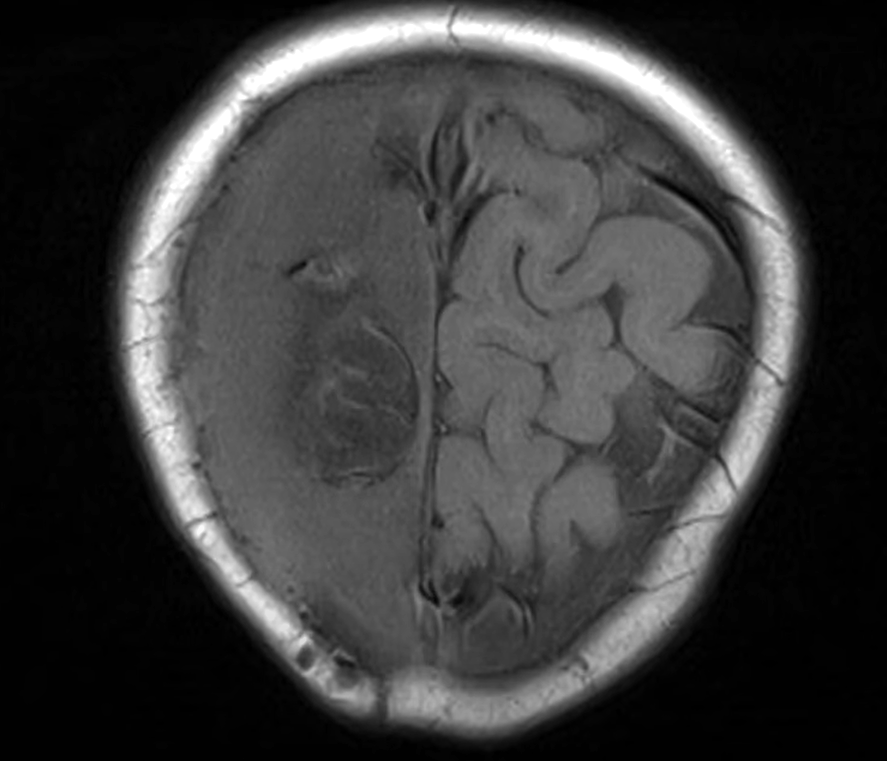

小雪兒的媽媽Amy在無綫節目《東張西望》中受訪表示,女兒獲院方安排接受重置頭骨手術。(《東張西望》畫面)

她又指目前還要面對其他問題,之前取出的骨頭儲存於雪櫃,「已冇晒生命」直接可以形容為「死骨」,再填補原位純屬保護作用,該塊骨可能會被身體當作外來物排斥,所以面對極大風險。另外,小雪兒目前腦部情況變壞,最新腦素描影像報告,「右邊紋路可能清晰,左邊則呈一片空白」,顯示左腦萎縮,故需要盡快手術。